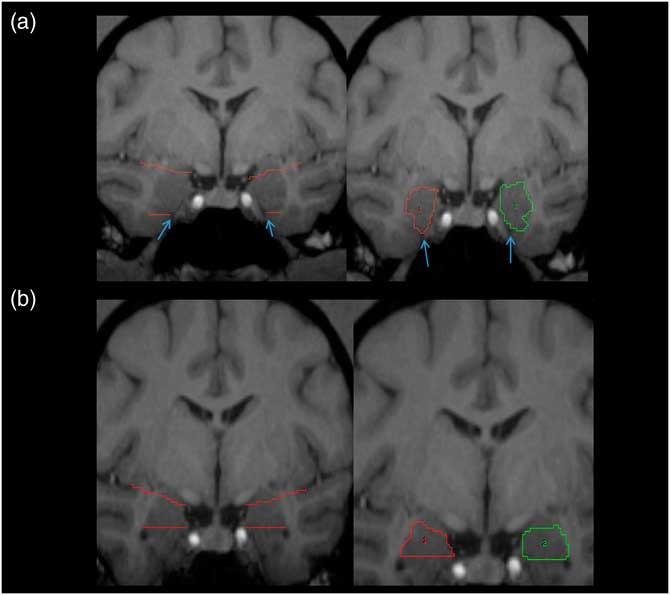

Tracing of the amygdala was primarily done in the coronal plane using the mouse-driven trace tool within Analyze 10.0 software. The slice where the optic chiasm fuses was the most anterior slice where the amygdala was present, and served as the anterior border. The tentorial indentation or WM tract was used as the inferior border on most scans, depending on which was most prominent. An imaginary line stretching from the endorhinal sulcus to the fundus of the inferior portion of the circular sulcus of the insula was used as the superior border (see Figure 1A). The WM was used as the lateral border and the 3rd ventricle as the medial border; the GM within these boundaries in both hemispheres was assumed to be part of the amygdala (see Figure 1A). Moving posteriorly, when the horns of the lateral ventricles appeared, the tentorial indentation (or WM track) was no longer used as the inferior border. Instead, the lateral horn was used as the inferior border, and any tissue below this landmark was considered part of the hippocampus (see Figure 1B). The most posterior slice was defined as the first slice within which the mammillary bodies appeared in the image.

Figure 1 Pictorial representation of amygdala. (A) Left panel: the white matter tracts and/or the tentorial indentation (blue arrows) are used as the inferior border. (B) Left panel: upper angled red lines represent the imaginary line from the endorhinal sulcus to the inferior portion of the circular sulcus of the insula, which was used as the superior border of the amygdala. Right panels: traced amygdala on most anterior (A) and posterior (B) slices, with landmarks removed. ROIs for right (1) and left (2) shown in red and green, respectively. For more details, see amygdala region of interest tracing methods text.